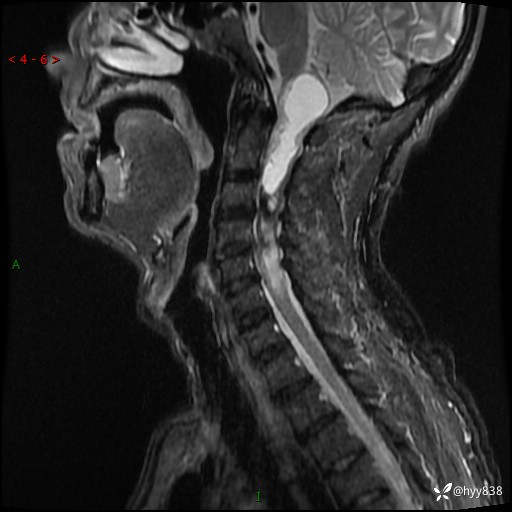

晨读典型病例分享。老年男性,右手麻木3年,四肢无力4月---结果公布~

主诉:右手麻木3年,四肢无力4月

简要病史:患者约于2年前无明显诱因出现右手麻木伴有精细活动差,无行走不稳,家属将患者送至当地县人民医院行颈椎MR提示:颈髓占位性病变。患者未系统治疗治疗。后病情逐渐加重,4个月前出现四肢无力,右侧为甚,行走不稳,伴有四肢感觉减退,伴有大便偶有失禁,现患者及家属为求进一步治疗入我院,遂以“椎管占位”收住我科。 发病以来,患者精神饮食睡眠好,大小便正常,体力体重未见明显改变。

辅助检查:MRI

临床诊断:椎管占位

讨论:病变性质?

颈椎MRI平扫(sag T1WI+T2WI-fs+axi T2WI)

CE